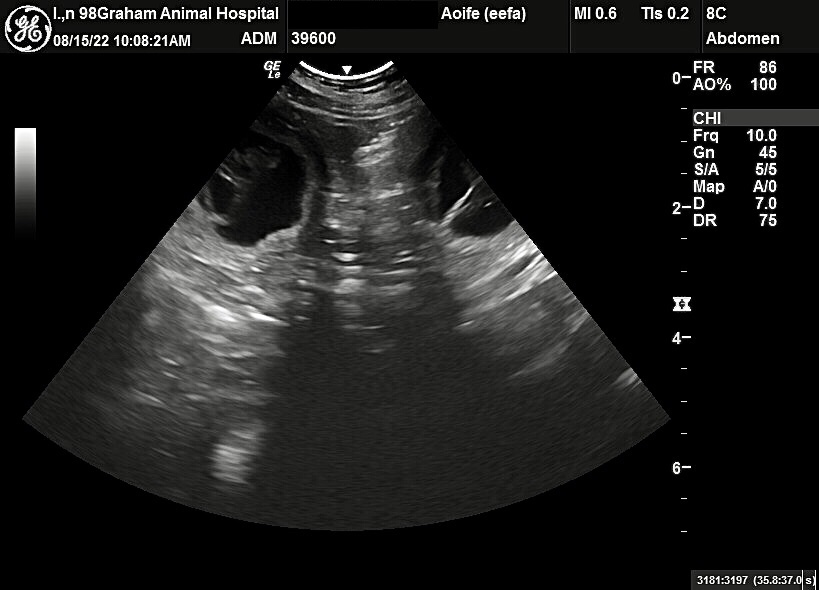

Aoife has been confirmed pregnant with Creed as the sire, and this F3 Pomsky puppy will be due September 16-18, 2022. This will be Aoife’s very first litter so we are super excited for her… and of course nervous as well, which means extra momsky helicoptering for her!